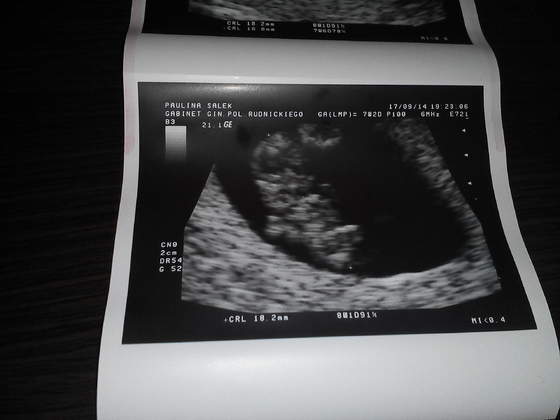

Slyszeliśmy jak bije serduszko naszej dzidzi

W środę idę na kolejną wizytę ale już na NFZ. Mam być na 7.00 to mnie gdzieś wciśnie w kolejkę żebym becikowe dostała. Lekarz bardzo fajny i chyba on mi będzie prowadził ciążę tylko nie wiem jak to będzie z dojazdami do warszawy ale jakoś dam radę